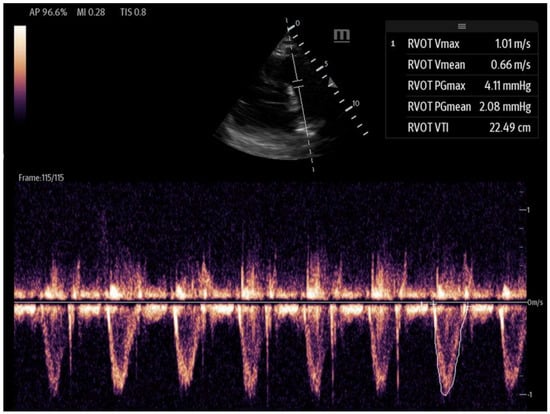

Figure 6. Tricuspid annular plane systolic excursion (TAPSE): apical 4-chamber view with M-mode activation, demonstrating reduced TAPSE (measured at the bottom 2D M-mode). - Right ventricular outflow tract velocity–time integral (RVOT-VTI): RV contractility can be evaluated using the RVOT-VTI, which represents the distance traveled by blood across the RVOT during systole. Stroke volume is calculated by multiplying the RVOT cross-sectional area by the RVOT-VTI. This measurement provides insight into both RV function and pulmonary vascular resistance, with an RVOT-VTI ≥ 12 cm considered normal [38] (Figure 7). The RVOT VTI is a better predictor of RV dysfunction in cardiogenic shock states compared to TAPSE and may also have prognostic value in patients with pulmonary hypertension [39,40].